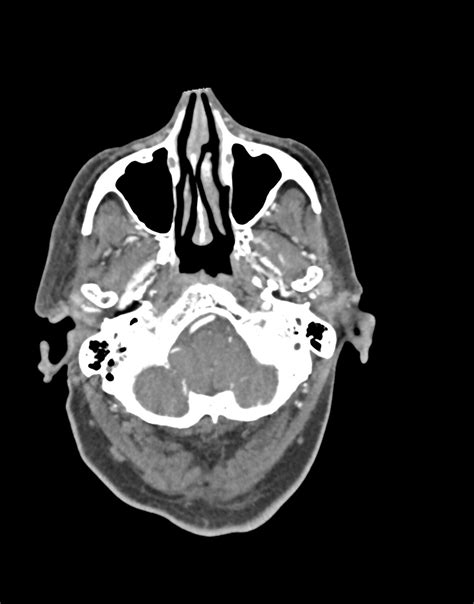

Diagnosing a Carotid Cavernous Fistula requires specialized imaging techniques to confirm the abnormal connection between the arteries and the venous sinus. Initial screenings often include:

• CT Angiography (CTA): Provides a high-resolution map of the vascular structures in the skull.

• Magnetic Resonance Imaging (MRI) and MRA: Useful for assessing the soft tissue and flow dynamics without ionizing radiation.

• Digital Subtraction Angiography (DSA): Considered the “gold standard” for diagnosis, this invasive procedure allows physicians to see the exact site of the fistula and plan for endovascular intervention.